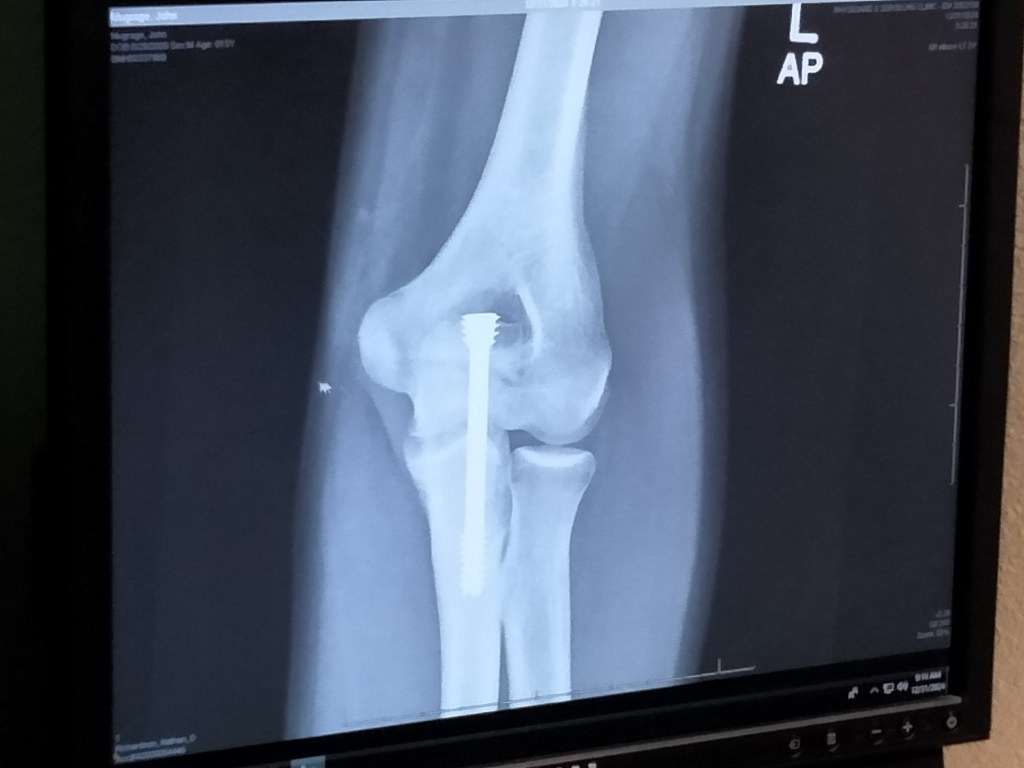

How It’s Going On January 13, 2025January 2, 2025 By Jennifer Mugrage I am now the proud parent of a minerally-enhanced athlete. Share this: Share on X (Opens in new window) X Share on Facebook (Opens in new window) Facebook Like Loading... Related